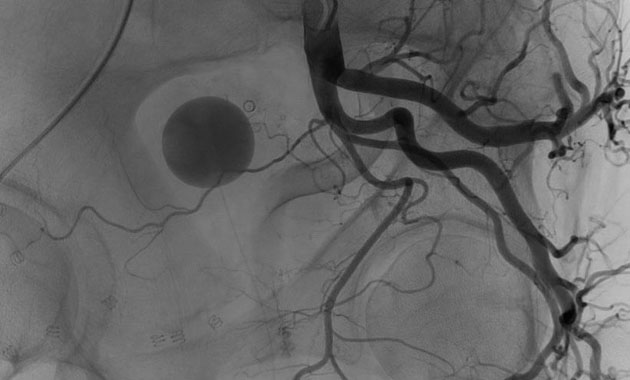

Prostate artery embolization (PAE) is a minimally invasive alternative to surgical procedures like TURP. PAE shrinks the prostate by treating its blood vessels. It is performed by an interventional radiologist through a small incision in the upper thigh.

Dr. Ryan Kohlbrenner and his team use specialized techniques to perform prostate artery embolization (PAE), a procedure being increasingly used in the United States to treat prostate gland enlargement and its associated urinary symptoms. Through a small incision in the upper thigh, access to the prostate's blood vessels is gained, and small particles are injected to slow the blood flow to the gland. In the weeks and months following PAE, the prostate relaxes and shrinks, resulting in symptom relief for most men. Although conventional prostate surgery can be associated with complications like impotence and incontinence, PAE is a minimally-invasive alternative that is not known to cause these issues. We are happy to now offer this procedure to UCSF patients.